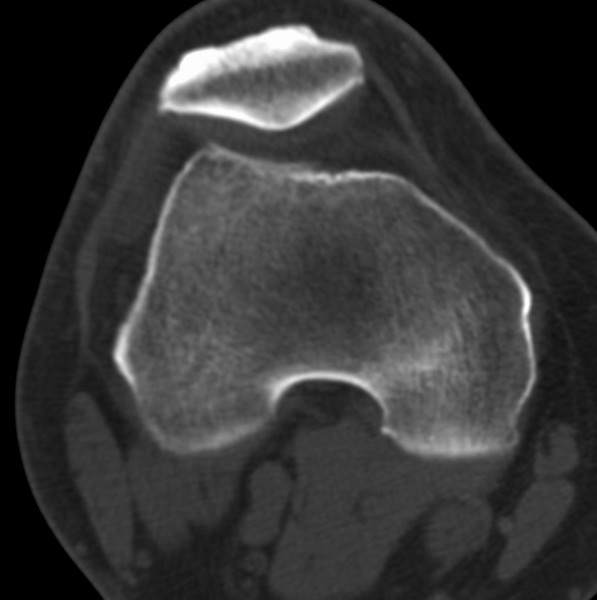

标题: CT21959:骨肿瘤请会诊。

右侧膝关节疼痛一月

男、48

股骨下段、胫骨上段。

1、股骨干骺端病变考虑干骺端纤维性皮质缺损愈后(非骨化性纤维瘤)改变,胫骨近端内生骨瘤(或干骺端纤维性皮质缺损愈后改变);

2、骨关节炎,骨质增生,股骨外侧髁退变性囊肿(关节面软骨下囊肿);

股骨干骺端病变考虑非骨化性纤维瘤。

1、股骨干骺端病变考虑干骺端纤维性皮质缺损愈后(非骨化性纤维瘤)改变,胫骨近端内生骨瘤;